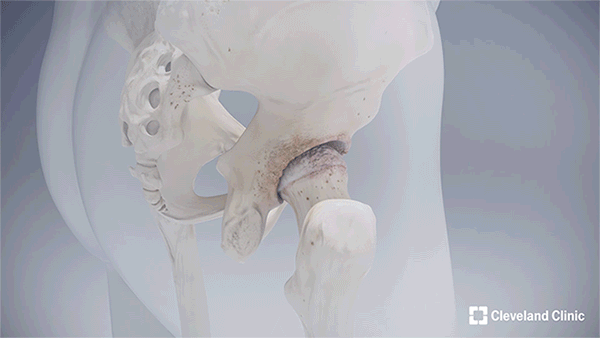

When the pain drove Georgina to get an MRI, it showed her femoral head – the rounded top of the thigh bone that fits into the hip socket – had collapsed due to avascular necrosis. This condition occurs when the blood supply to the bone is disrupted, causing bone tissue to die. In her case, the damage likely stemmed from dislocating her hip years ago.

“While a great option, a total hip replacement is not the best approach for everyone. For instance, it can reduce the amount of exercise a patient can take. So, despite not having any more pain following the procedure, it’s not recommended they return to activities like running, for example,” says Prof Cobb. “With hip resurfacing, patients retain the femoral head and neck, allowing them to resume the activities they participated in with their healthy, native hip.”

Georgina came to Prof Cobb at the right time. For years, the only available option was metal-on-metal hip resurfacing, which manufacturers currently recommend only for patients with larger femoral heads – typically found more often in men. This design is less suitable for individuals with smaller bone structures, including many women and others with narrower hips, who are more likely to experience pain and require early revision after the procedure. In response to this limitation, Prof Cobb and a team of developers created an innovative ceramic hip resurfacing implant called the H1, tailored specifically for patients with smaller hips and pelvises.